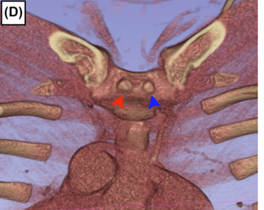

图D:左侧头臂静脉周围骨骼与软组织关系示意图(黄色:骨骼结构;红色:软组织)